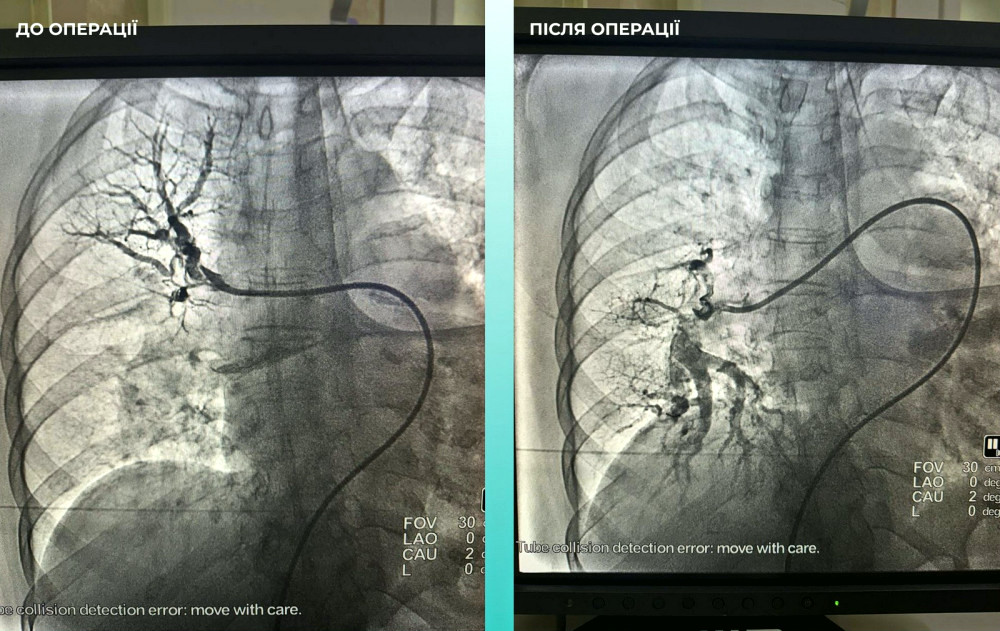

Команда фахівців ухвалила рішення про проведення одночасної тромбектомії обох артерій, що стало критично важливим кроком.

Операція завершилась успіхом: пацієнтка почувається набагато краще, вона вже в свідомості та може рухати кінцівками.